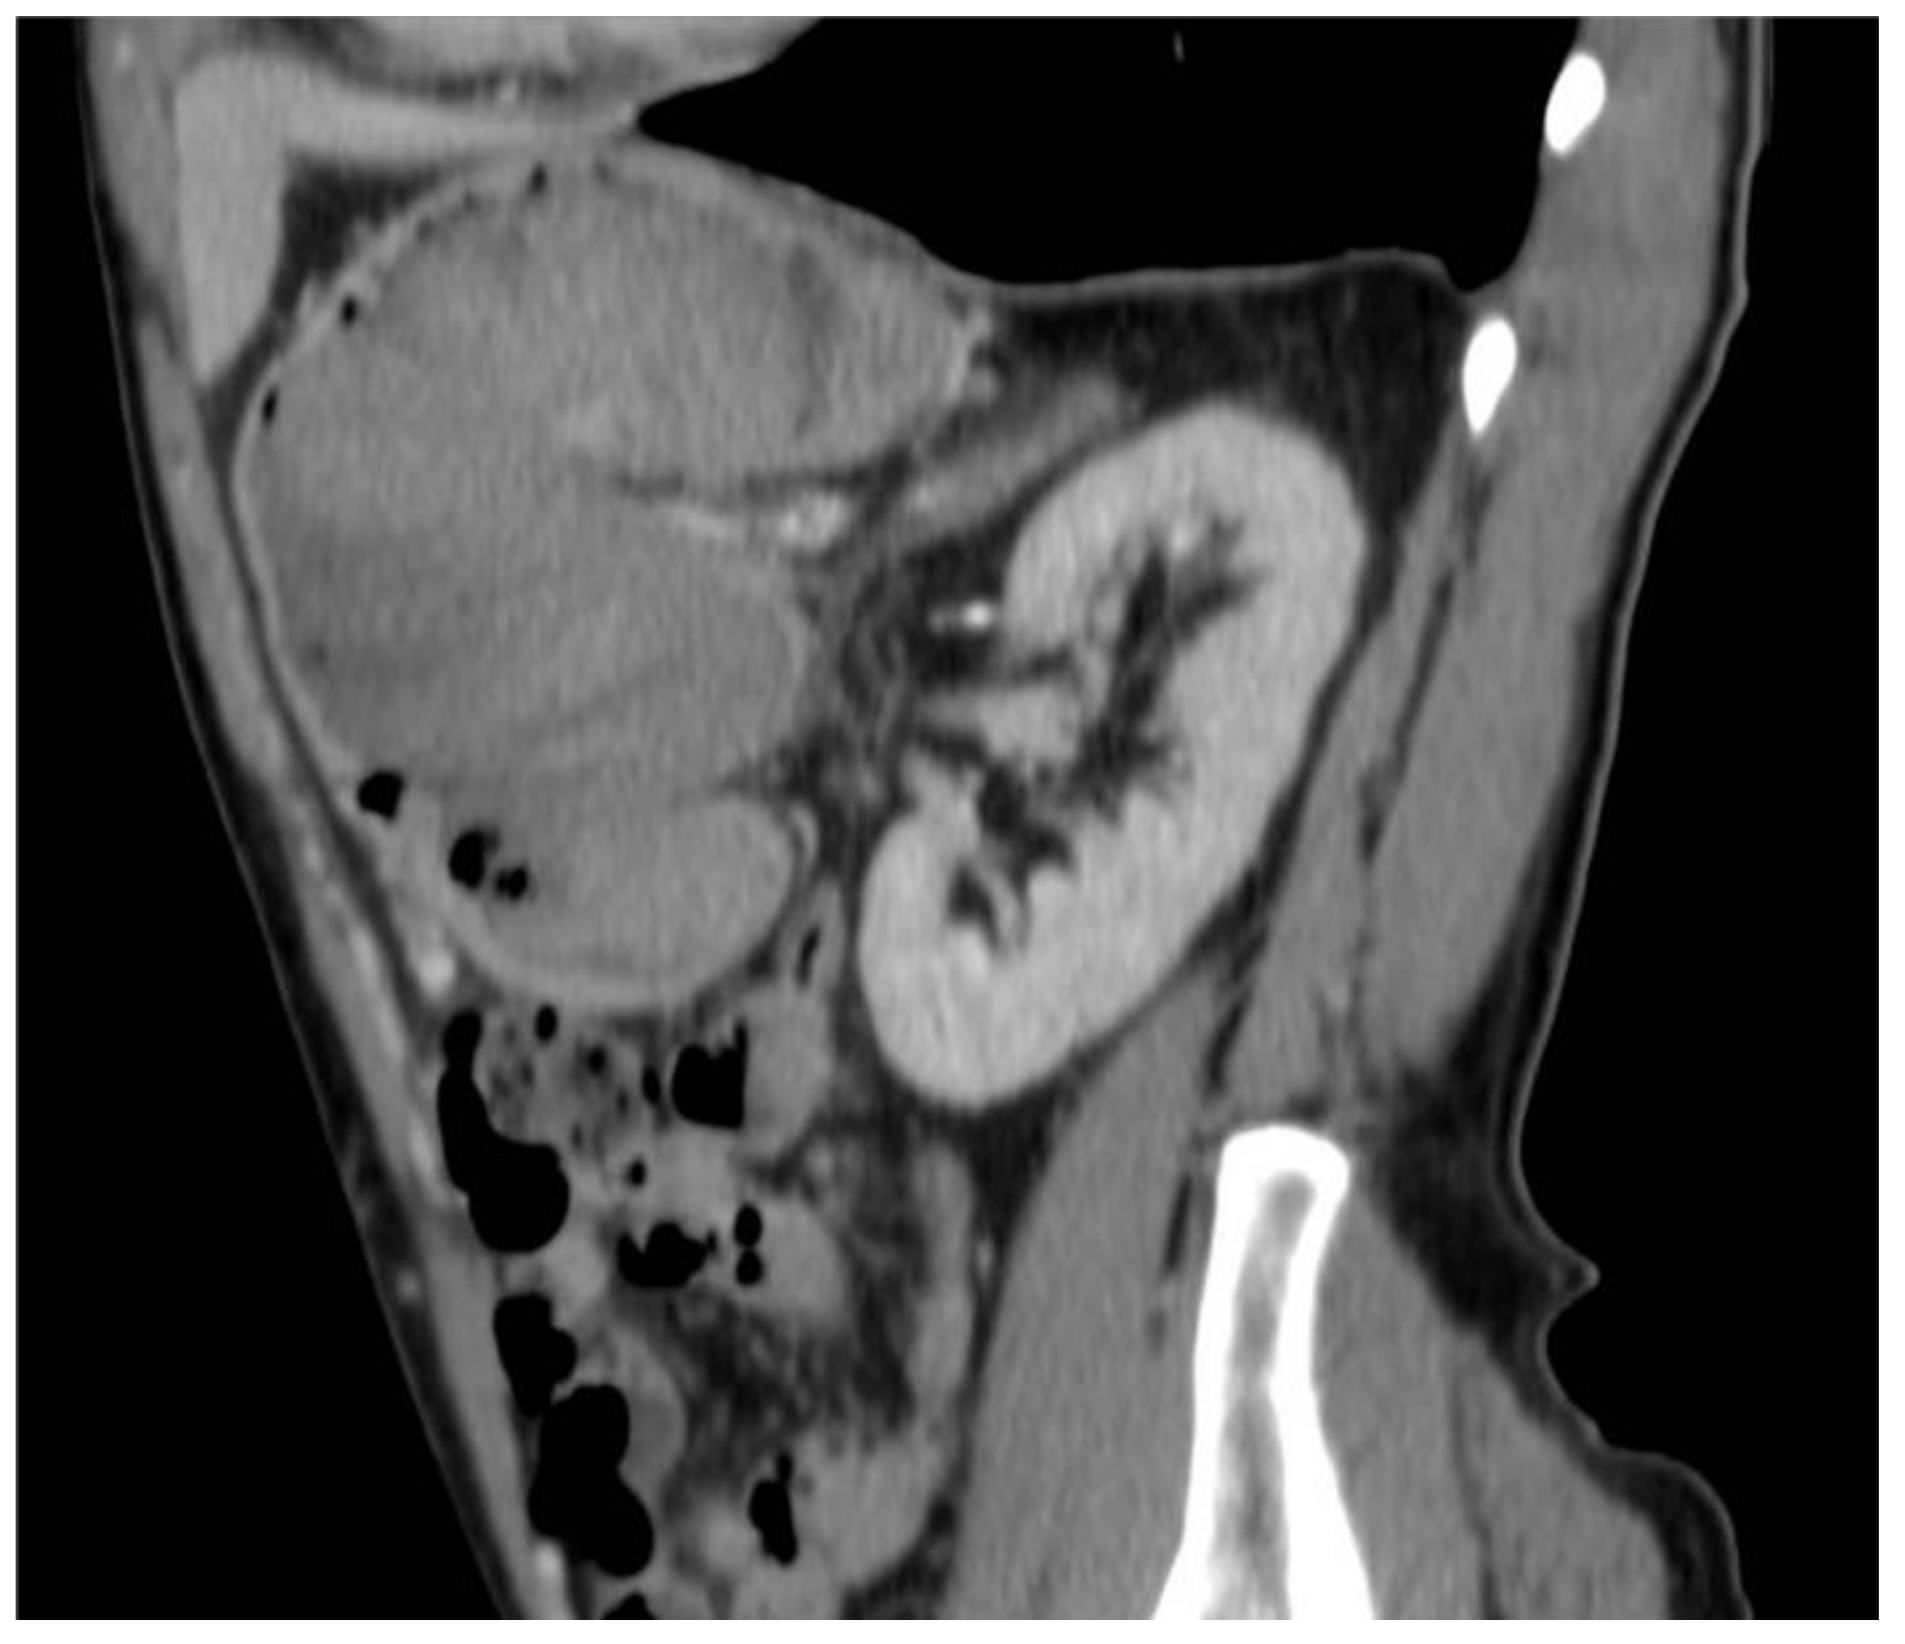

2. Case Report